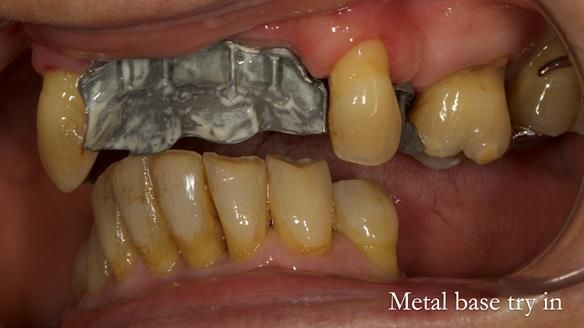

In this edition, I present the removable partial denture treatment for Jean, an 80-year-old woman with a sore mouth caused by a soft tissue-supported 'gum stripper' acrylic denture and a clenching habit. Below, I outline the step-by-step process of her treatment. It wasn't straightforward; I had to remake the denture after it fractured to achieve a satisfactory result. Each patient is unique, and sometimes a new RPD serves as a prototype. Occasionally, I need to make adjustments, learn from any mistakes, and refine the design to get it right.

The treatment has been a success over the past 4 years.